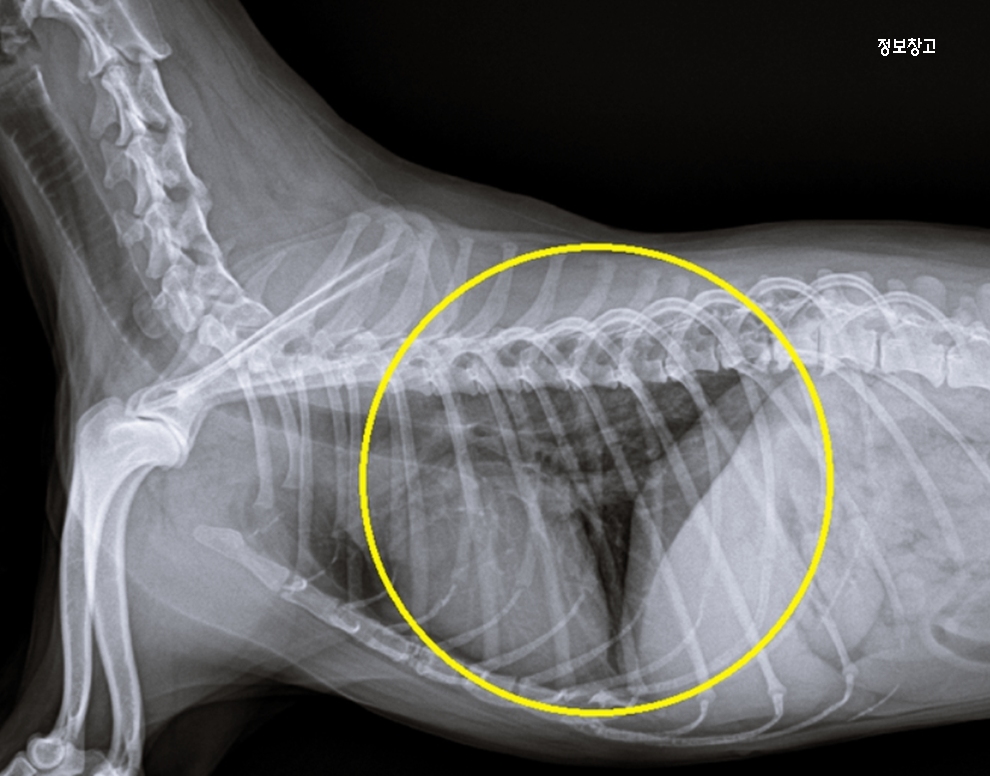

🔸 ③ 심장 문제(심장판막질환 초기)

기침이 밤이나 새벽에 심해짐

운동 후, 흥분했을 때 기침 발생

기침이 길고 끊기지 않는 경향

호흡 속도가 빨라짐

👉 특징:

기침 전에 호흡이 거칠거나 배로 숨을 쉬는 모습.

🔸 심장 문제 의심될 때

과한 운동 금지

계단·점프 줄이기

호흡수 체크 습관화

👉 강아지의 기침은 단순한 감기가 아니라

심장 질환의 초기 신호일 수 있기 때문에 방치하면 위험해질 수 있어요.